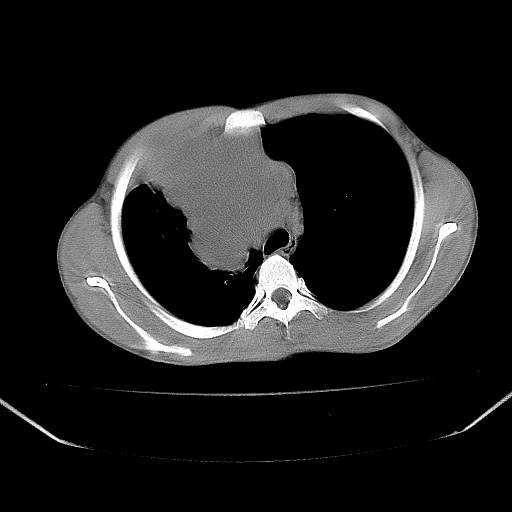

以下是引用zjzjr在2008-7-20 12:57:00的发言:[br]考虑为生殖源性肿瘤(内胚窦瘤),侵袭性胸腺瘤可能性大;右侧少量胸腔积液。

以下是引用xinliheng001在2008-7-20 21:17:00的发言:[br]右纵隔巨大分叶状软组织均质密度肿块,右上肺叶受压明显,纵隔右移、胸膜受累有少量积液和结节样增厚。应增强扫描一定会有更具诊断价值的信息。

以下是引用xinliheng001在2008-7-20 21:17:00的发言:[br]右纵隔巨大分叶状软组织均质密度肿块,右上肺叶受压明显,纵隔右移、胸膜受累有少量积液和结节样增厚。应增强扫描一定会有更具诊断价值的信息。